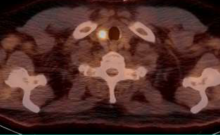

Siemens Healthcare has introduced Biograph mCT Flow, a positron emission tomography/computed tomography (PET/CT) system that, for the first time ever, overcomes the limitations of conventional bed-based PET/CT with FlowMotion, a revolutionary new technology that moves the patient smoothly through the system’s gantry, while continuously acquiring PET data. Biograph mCT Flow with FlowMotion takes routine image quality to a new level by enabling imaging protocols based on the organ’s need.